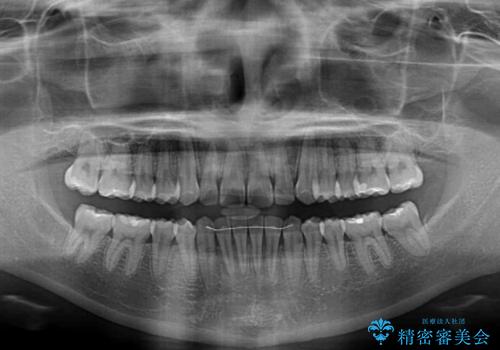

咬合高径の挙上により上顎前歯の突出感も改善することができ、整った口元となりました。